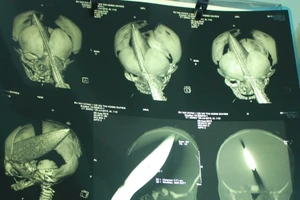

Sức khỏe bé trai bị đâm xuyên não thế nào khi 2 tuổi?

Kẻ lạ mặt đâm dao vào đầu bé trai 11 ngày tuổi ngay tại bệnh viện